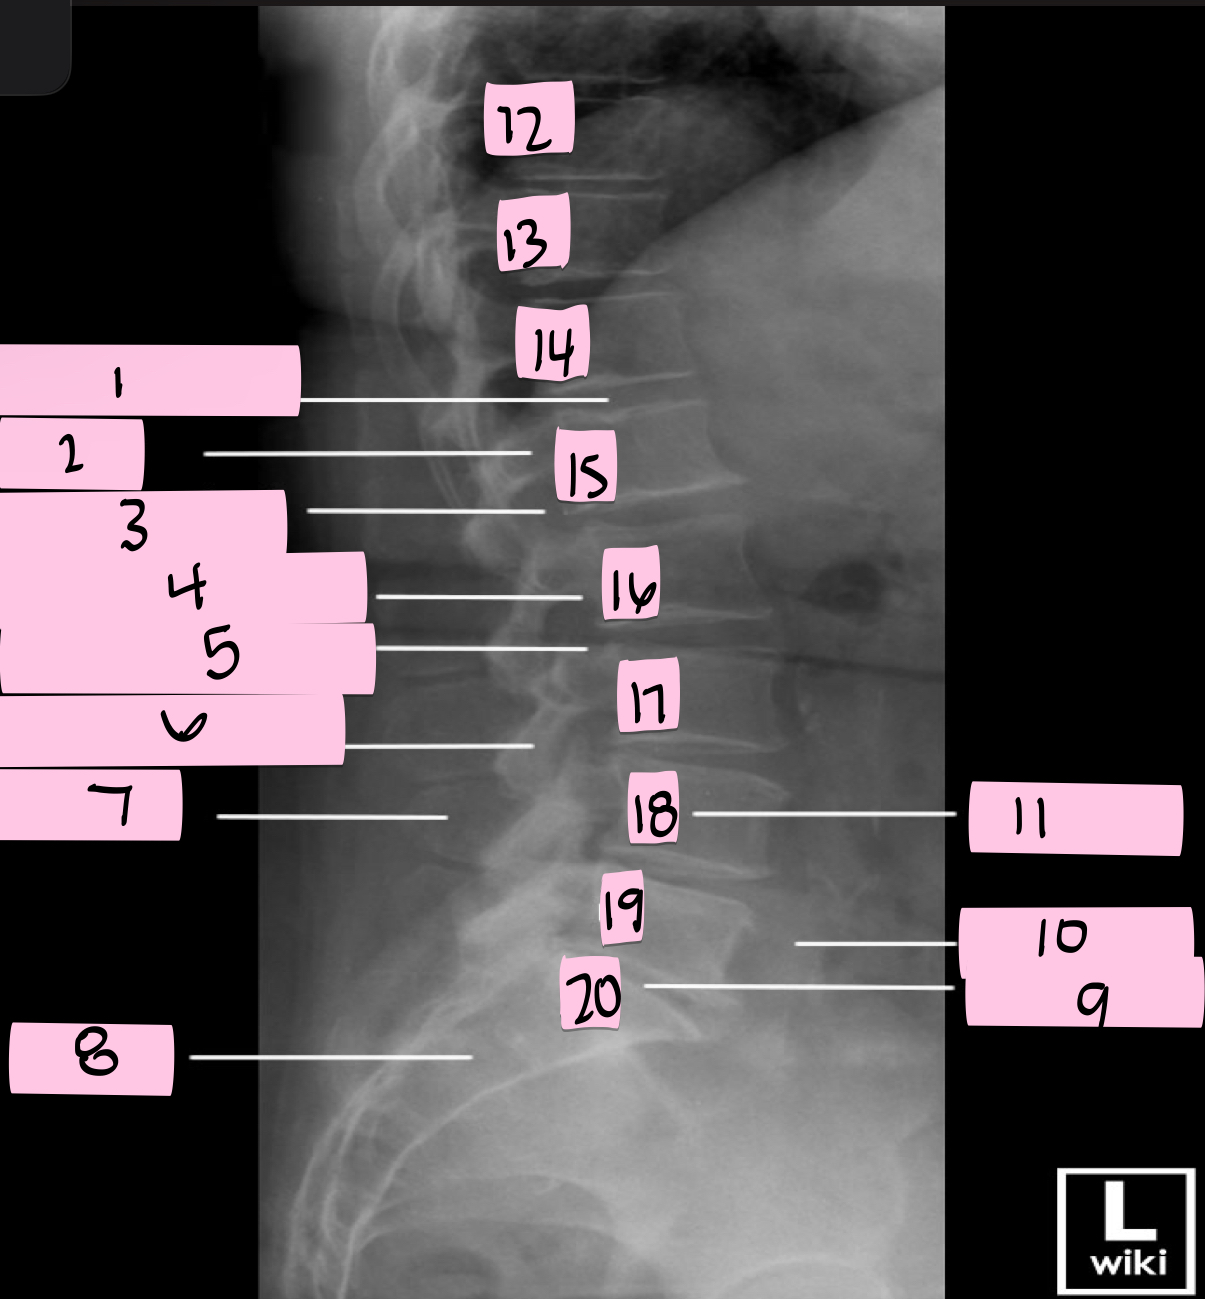

What is 1 pointing to?

Intervertebral disk

What is 2 pointing to?

Pedicle

What is 3 pointing to?

Intervertebral foramen

What is 4 pointing to?

Inferior vertebral notch

What is 5 pointing to?

Superior vertebral notch

What is 6 pointing to?

Inferior articular process

What is 7 pointing to?

Spinous process

What is 8 pointing to?

Sacrum

What is 9 pointing to?

L5 S1 joint

What is 10 pointing to?

Iliac crest

What is 11 pointing to?

Vertebral body (L4)

What is 12 pointing to?

T10

What is 13 pointing to?

T11

What is 14 pointing to?

T12

What is 15 pointing to?

L1

What is 16 pointing to?

L2

What is 17 pointing to?

L3

What is 18 pointing to?

L4

What is 19 pointing to?

L5

What is 20 pointing to?

S1